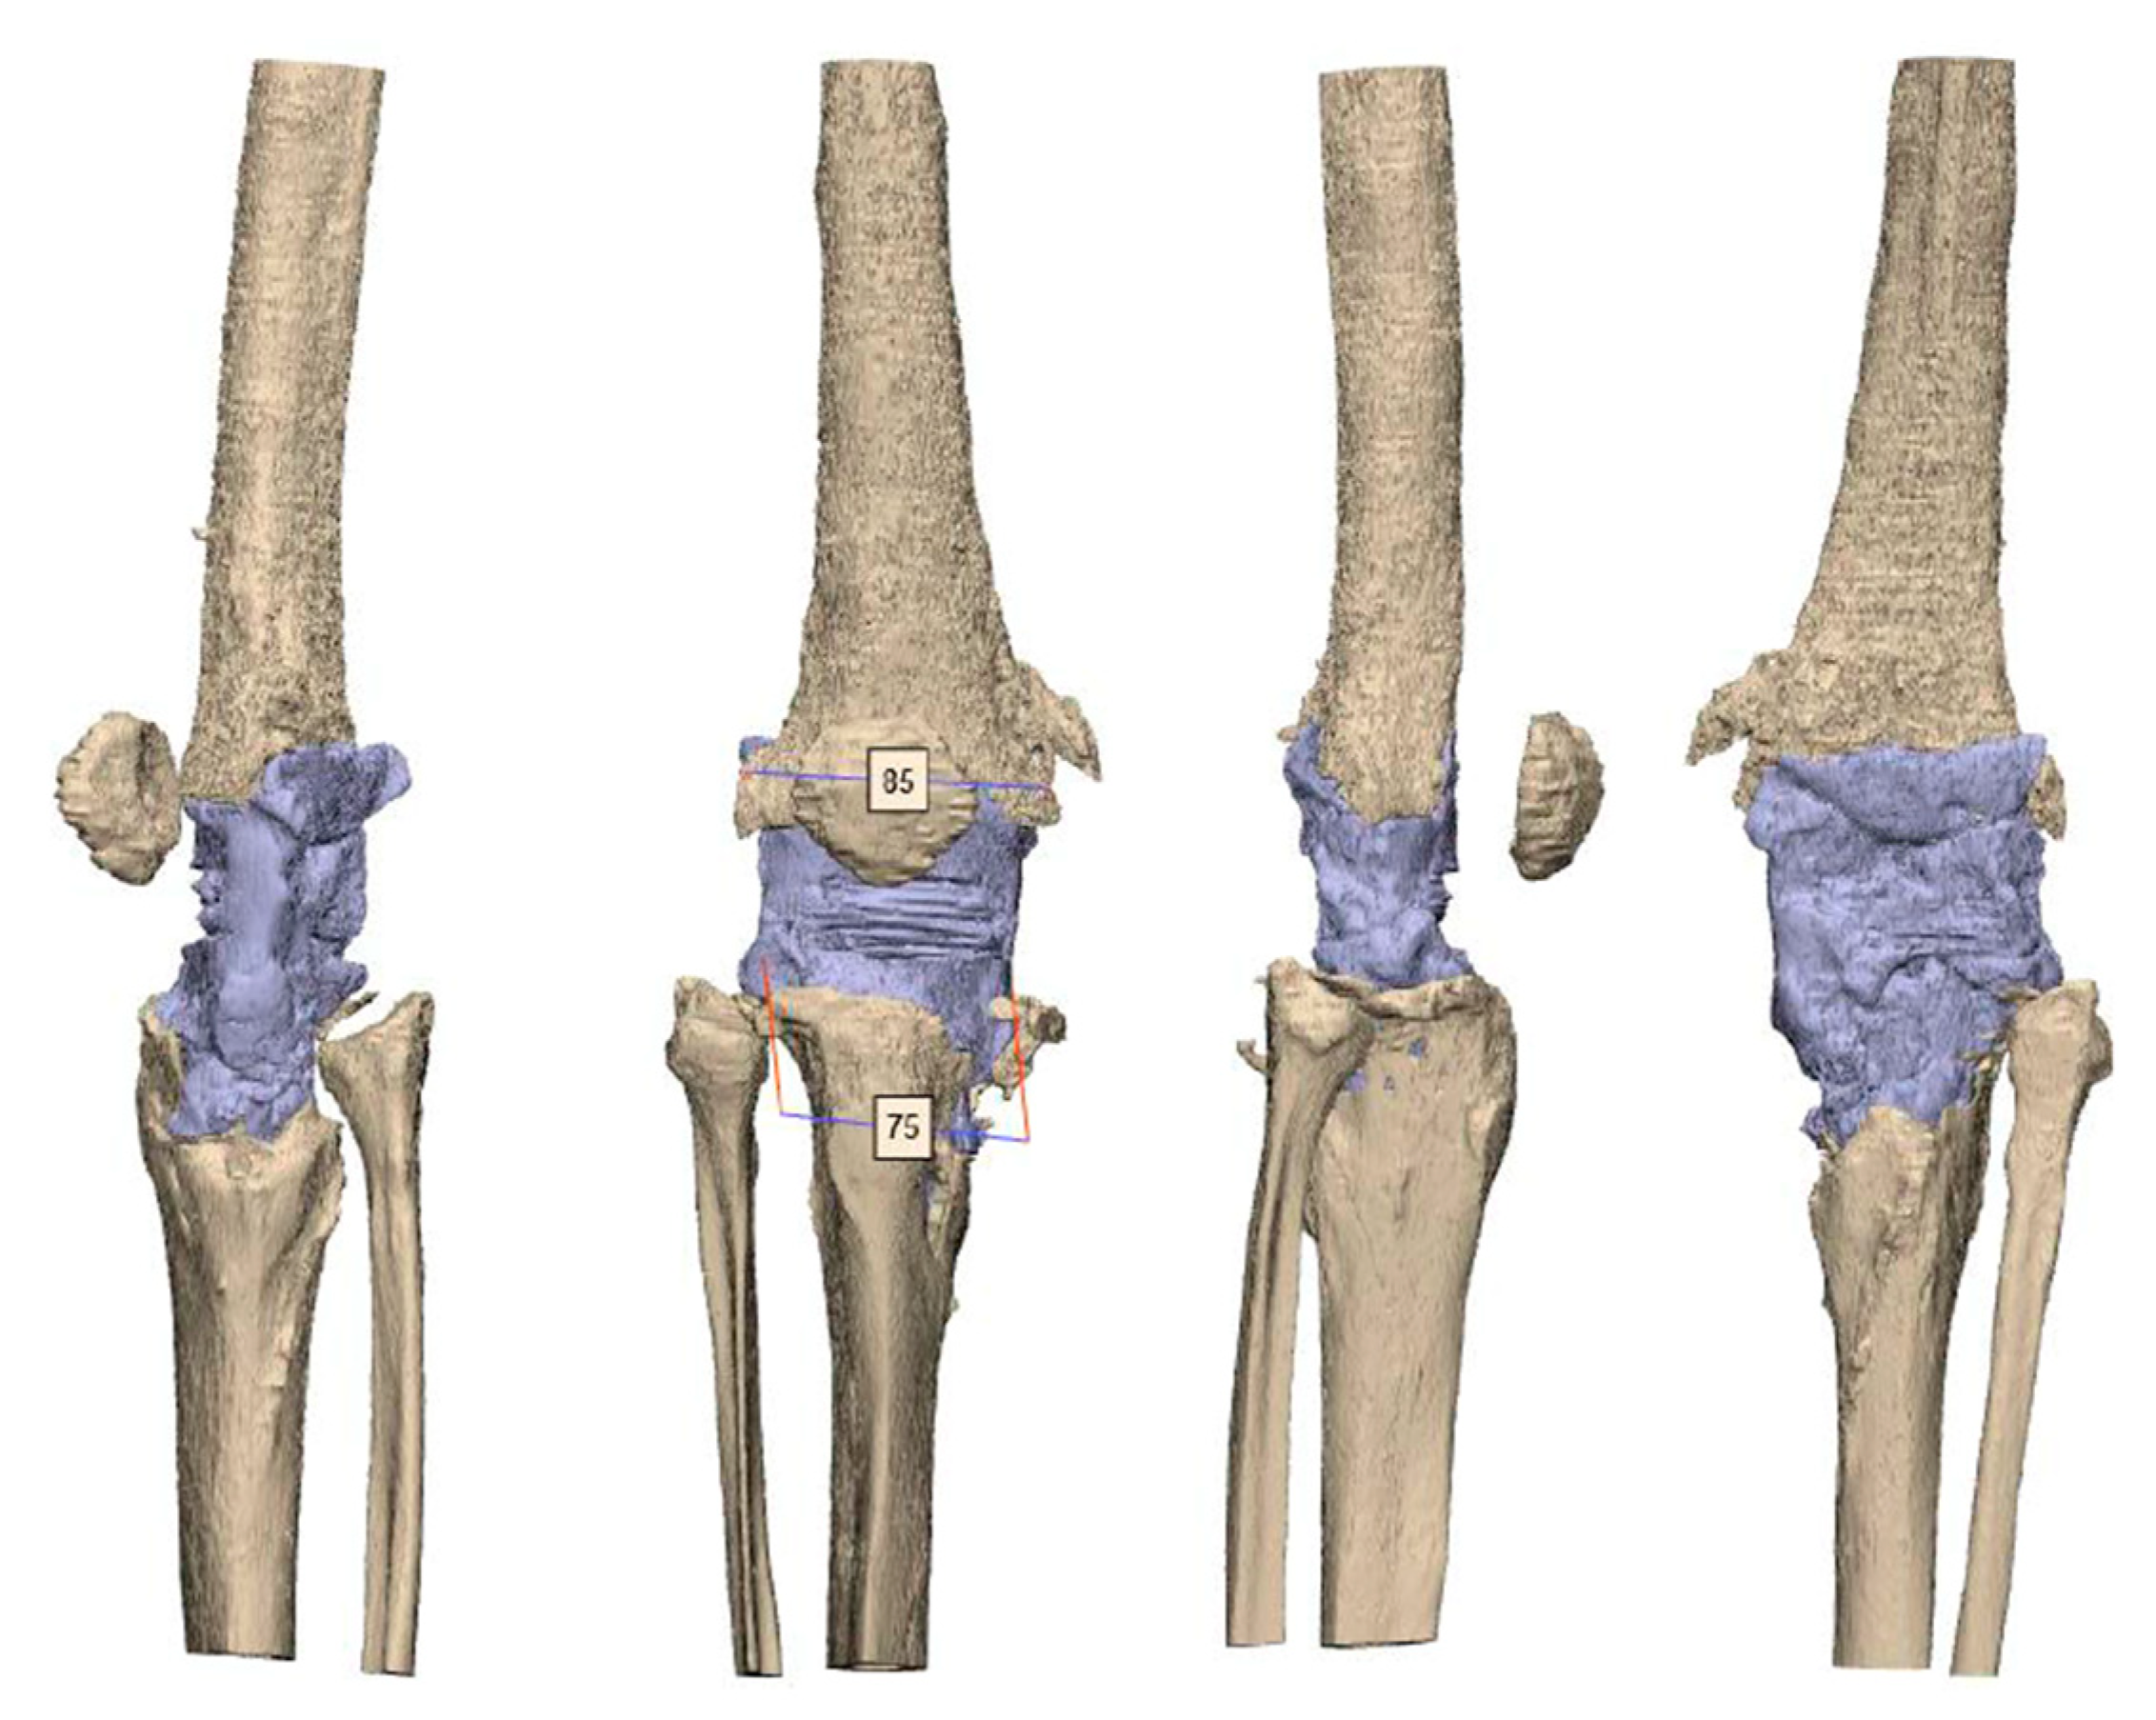

After segmentation, the first step of planning is the analysis of the bone defect (Figure 2). If the defect of the distal femur is too devastating, resection of the distal femur may be necessary. In such a scenario, the use of a conical oval stem is advisable (Figure 3). If the tibial tuberosity is still intact, proximal tibial replacement may not be required. With the help of a tibial cone, a standard tibial implant can be used. The cone provides a bearing surface to reconstruct the joint line (Figure 4). If iatrogenic fractures occurred during the first operation, this should be taken into account when planning the stem length. Features such as notches for cerclages or additional attachment options for the extensor mechanism are possible after consultation with the engineers (Figure 5 and Figure 6D).

Figure 2.

CT scan after the explantation of the septic prosthesis with a huge bone defect on the metaphysis of the tibia and femur. The tuberositas tibiae is still intact. However, the medial tibia plateau is loss. AO fixature bars are used for the rigid spacer. The mediolateral size for the femur is 85 mm and for the tibia 75 mm.